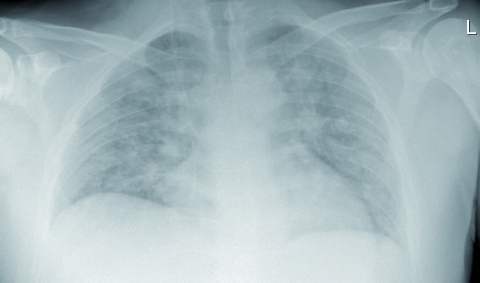

Die Röntgenaufnahme des Thorax zeigte pneumonische Infiltrate beidseits ohne Nachweis von Kavernen (Abbildung 2). CT[4] Thorax und Abdomen mit Kontrastmittel erbrachten den Nachweis fein- und grobfleckiger pneumonischer Infiltrate und Pleuraergüsse beidseits sowie eine Hepatosplenomegalie. Im MRT[5] BWS/LWS (nativ und mit Kontrastmittel) stellte sich das Bild einer isolierten Spondylitis des BWK 11 mit zirkulärer paravertebraler Entzündungsreaktion ohne spinale und Diskusbeteiligung dar (Abbildung 3). Der Ausschluss von Herzklappenvegetationen erfolgte durch eine transösophageale Echokardiographie. Bronchoskopisch wurde zäh-putrides Sekret für die mikrobielle Untersuchung gewonnen; infektiologisch konnten Malaria, Tuberkulose, Brucellose, Leptospirose, Hepatitis, eine HIV- und Legionelleninfektion ausgeschlossen werden. Die Sonographie des Abdomens war bis auf eine Hepatosplenomegalie unauffällig. Laborchemisch fielen bei Aufnahme erhöhte Entzündungswerte, eine Linksverschiebung im Differential-blutbild sowie